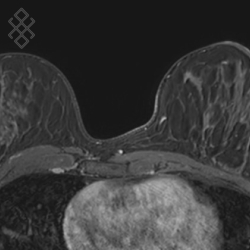

Vous entrez dans l'IRM les pieds en premier et vous êtes allongées à plat ventre sur une antenne avec un sein dans chaque "trou". Étant donné que cet examen est bruyant, vous aurez à votre disposition des tampons auriculaires pour atténuer le bruit de la machine.